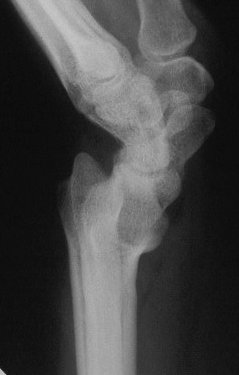

Case 3. Adult bilateral congenital Madelung's deformity with pain and extensor tendinitis, treated with the Sauve Kapandji (Lauenstein) procedure: segmental distal ulnar ostectomy and distal radioulnar joint fusion.

And the left side, preop: